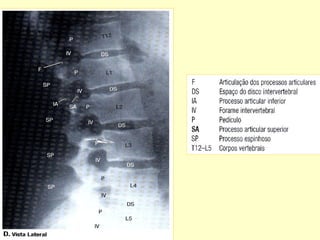

C – Vista Lateral

Incidências Básicas

Radiografias em A P e Perfil .

Para verificações dos forames intervertebrais

como também para avaliação dos arcos

posteriores , acrescentar incidências obliquas.